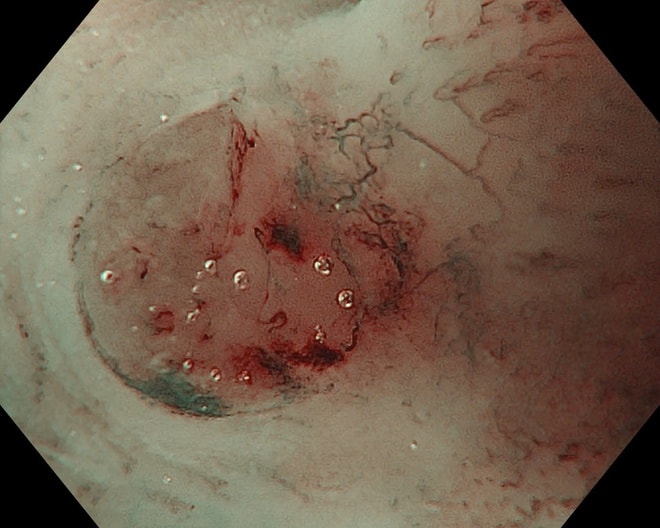

Hình ảnh tổn thương thực quản của bệnh nhân.

Các bác sĩ Bệnh viện K sử dụng hệ thống máy nội soi nội soi nhuộm màu phóng đại Olympus EVIS X1 hiện đại nhất giúp hình ảnh sắc nét, hiển thị rõ tổn thương dù là nhỏ nhất, có chức năng nhuộm màu bằng ánh sáng và phóng đại trên 150 lần, giúp phân tích rõ ràng vi cấu trúc và vi mạch máu của tổn thương, đưa ra nhận định chính xác về tính chất tế bào học của tổn thương, phân biệt tổn thương ung thư và không ung thư từ đó đưa ra hướng can thiệp kịp thời cho người bệnh.

Một bệnh nhân 63 tuổi đã được phát hiện ung thư thực quản giai đoạn sớm nhờ công nghệ này và điều trị thành công, xuất viện sau 2 ngày.

Trong một trường hợp khác, bệnh nhân 67 tuổi được phát hiện tổn thương qua nội soi công nghệ cao. Tuy nhiên, qua đánh giá chuyên sâu, bác sĩ xác định tổn thương đã vượt chỉ định điều trị nội soi và chuyển sang phẫu thuật.

Kết quả mô bệnh học sau đó xác nhận ung thư đã xâm lấn dưới niêm mạc, phù hợp với chỉ định ngoại khoa.

Thực tế này cho thấy vai trò quan trọng của nội soi công nghệ cao kết hợp với kinh nghiệm lâm sàng trong việc đánh giá chính xác giai đoạn bệnh, từ đó đưa ra phương pháp điều trị phù hợp, tối ưu.